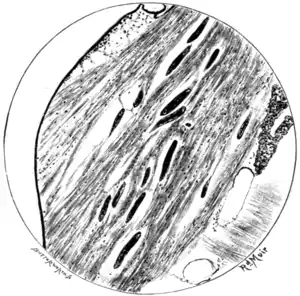

Fig. 103.—Section of thoracic muscles of mosquito seven days after it had fed on a filariated patient. (From a microphotograph by Mr. Spitta.)

quitted the stomach and entered the thoracic muscles of the insect, among the fibres of which they are now moving languidly. (Figs. 102-8.) By a course of serial dissections of filariated mosquitoes we can ascertain that in the thorax of the insect the parasite enters on a metamorphosis which takes from twelve to twenty days (longer or shorter, according to atmospheric temperature) to complete—a metamorphosis eventuating in the formation of a mouth, of an alimentary canal, and of a peculiar trilobed caudal end, as well as in a relatively